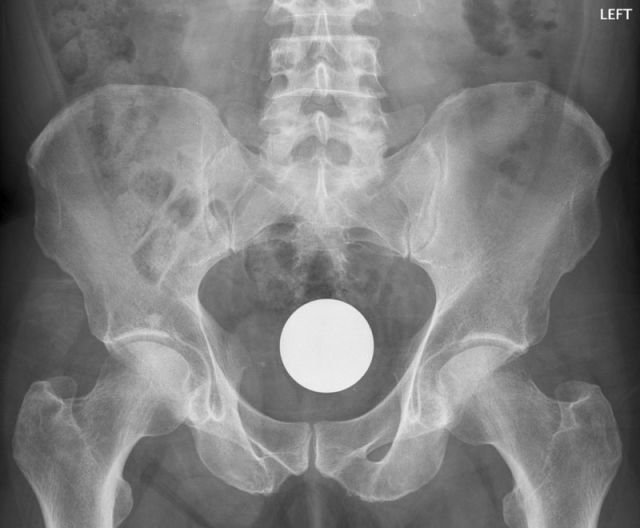

Billiard Ball